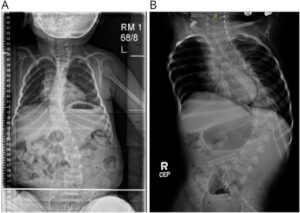

Clin Practice 2022より引用

背中の筋力が低下するため側弯が出現することが多いです。

筋ジストロフィーにでる側弯に似ています。

重症型や中間型のお子さんの多く見られ、あまり背骨の曲がり強いと座位に悪影響します。

側弯が高度の場合は装具を使うことがあります。

呼吸の問題や歩かないなどの運動レベルから側弯の手術が行われることは少ないです。